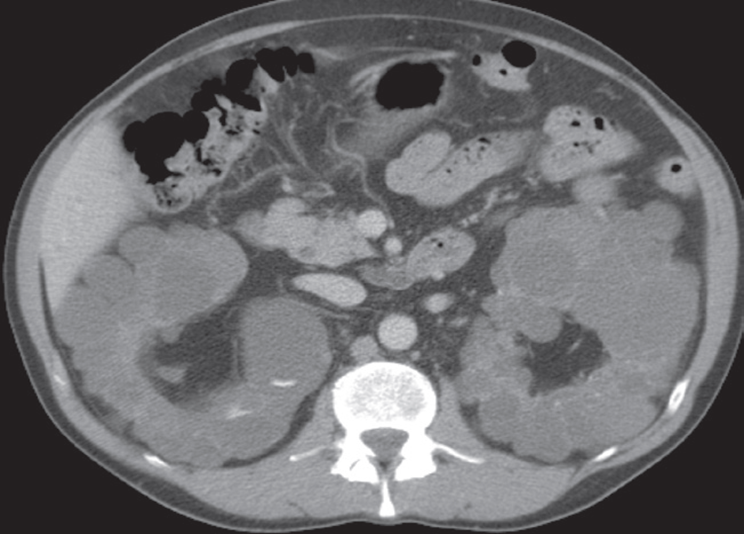

Advanced polycystic disease in adults. (a) CT scan,

taken after intravenous contrast enhancement, showing that both kidneys are greatly enlarged and almost entirely replaced by cysts of variable size.